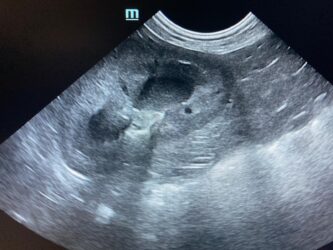

Dimitri, CV, 9.6kg, 11j, MC, bijgeruis 4/6 waarvoor hij vetmedin krijgt en opgevolgd wordt door cardioloog:

21/08/2025: Bij buurtcollega aangeboden voor hematurie. Plast vlot, op’t einde bloed te zien. Mevr. kookt zelf voor hem. Echo gehad + UOZ (geen idee hoe dit werd gecollecteerd) gedaan. Veel bloed in de…